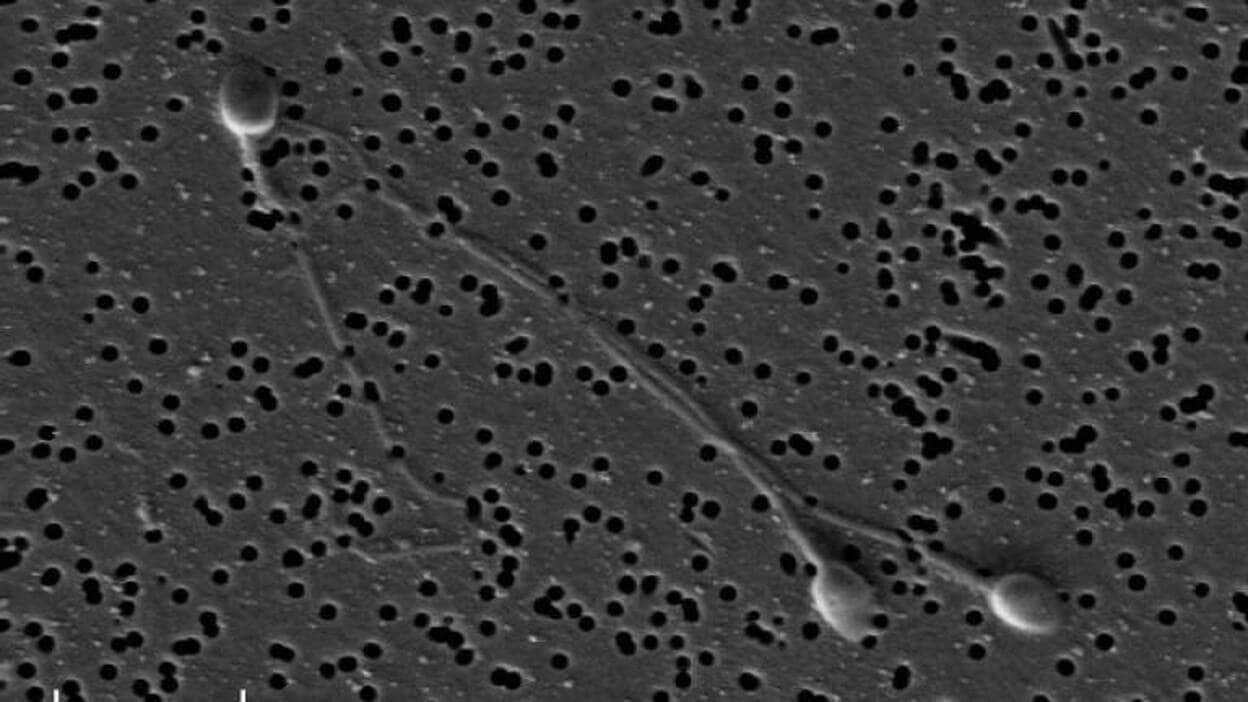

Científicos de la Universidad de Cambridge, en Reino Unido, que trabajan con el Instituto Weizmann, en Rehovot, Israel, han creado células germinales primordiales, células que pasarán a convertirse en óvulos y espermatozoides, empleando células madre de embriones humanos. Aunque esto ya se había hecho con células madre de roedores, el estudio, que se publica en la revista 'Cell', es el primero que lo consigue de manera eficiente empleando células madre humanas.

Cuando un óvulo es fertilizado por un espermatozoide, comienza a dividirse en un grupo de células conocidas como blastocistos, la etapa temprana del embrión. Dentro de esta bola de células, algunas células forman la masa celular interna, que se desarrollará en el feto, y otras crean la pared exterior, que se convierte en la placenta.

Las células de la masa celular interna se 'reinician' para convertirse en células madre, células que tienen el potencial de convertirse en cualquier tipo de célula en el cuerpo. Un pequeño número de estas células se transforma en células germinales primordiales (PGC), que pueden convertirse en células germinales (espermatozoides y óvulos), que en la vida más tarde pasarán la información genética a su propia descendencia.

El grupo demostró que las PGC también se podrían hacer a partir de células adultas reprogramadas, como las células de la piel, lo que permitirá a las investigaciones sobre células específicas del paciente avanzar en el conocimiento de la línea germinal, la infertilidad y los tumores de células germinales humanas.